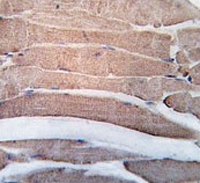

IHC testing of FFPE human skeletal muscle tissue with Death-associated protein kinase 2 antibody. HIER: steam section in pH6 citrate buffer for 20 min and allow to cool prior to staining.